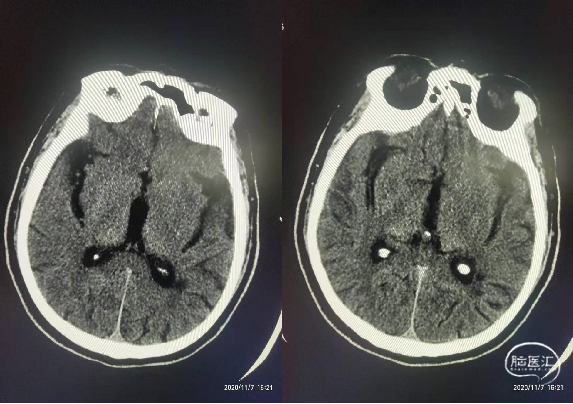

将6F Neuron Max长鞘置于左侧颈内动脉C2段,微导丝微导管引导下将ACE68抽吸导管置于左侧大脑中动脉M1段开口处,退出微导丝,置入4*20mm支架,支架远端位于M2段,释放支架等待5分钟。

支架释放5分钟后在持续负压抽吸下,采用抽吸导管抽吸结合支架取栓技术取出约4cm血栓1枚,术毕即刻造影左侧颈内动脉、大脑中动脉、大脑前动脉血流完全再通,mTICI评分3级。

术后第二天复查CT左侧基底节区脑梗死。